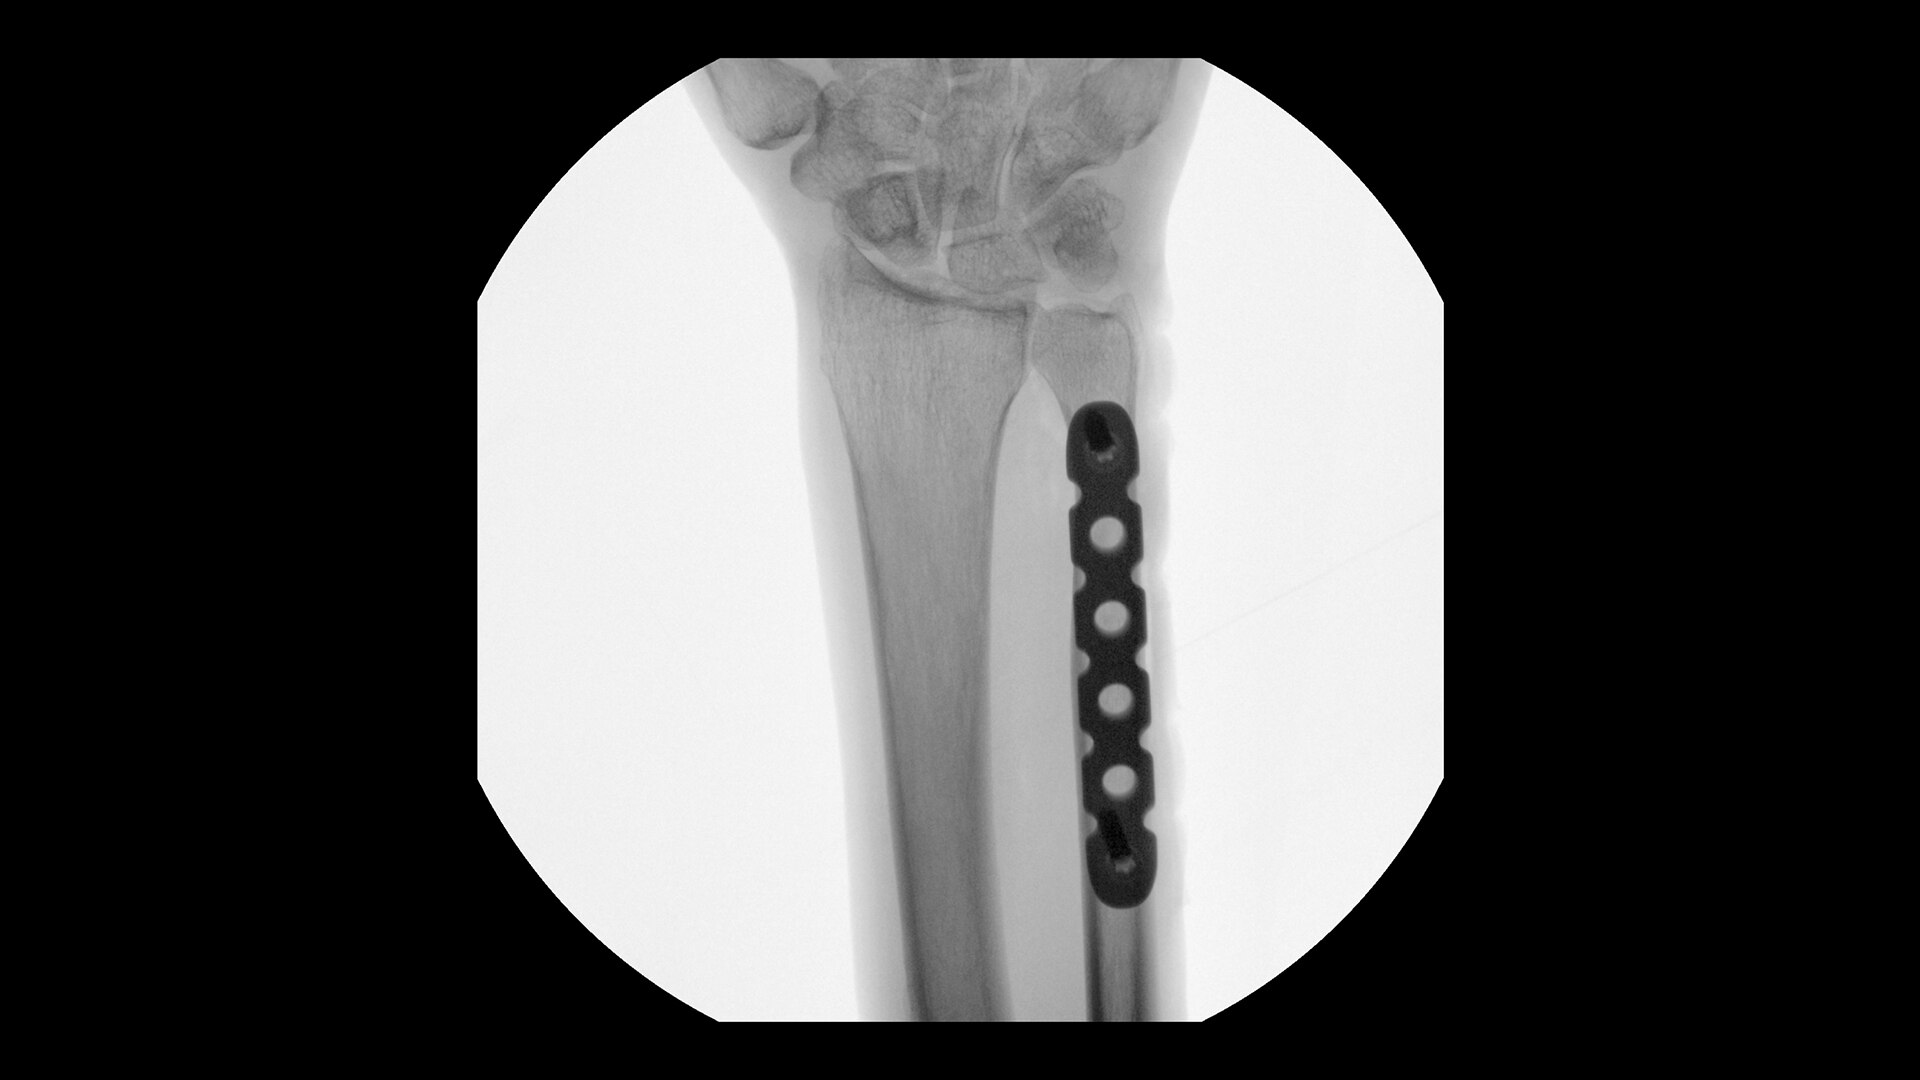

Revolutionary, deep-learning based reconstruction technology provides sharper, clearer, and accurate images

AIR™ Recon DL challenges the inherent trade-off between SNR, scan time and image resolution. Using a deep-learning based reconstruction algorithm, AIR™ Recon DL improves SNR by making use of the raw data to remove image noise and ringing. You can now produce high-quality images with shorter scan times, enabling greater patient throughput and increased return on investment.

With AIR™ Recon DL, the Precision Imaging Center saw approximately 50% less scan time for the musculoskeletal area.